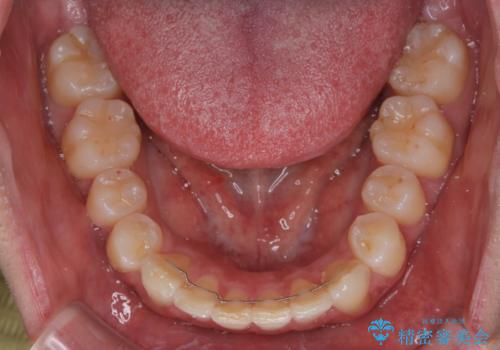

- 前歯のデコボコを治したいとのことで来院された患者様です。

上下顎ともに歯列全体の後方移動とIPR(歯と歯の間を削る)によってデコボコが解消するように設計し、インビザラインにより治療を行うこととしました。

下顎前歯は後戻りを起こしやすいため、舌側を細いワイヤーで固定し、マウスピース型リテーナーで保定を行うこととしました。